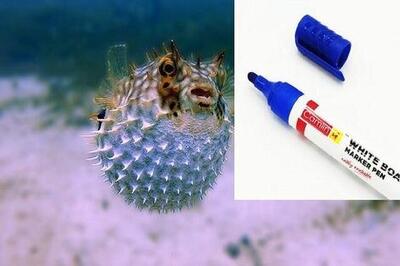

ماژیکی که با سم ماهی بادکنکی پر شده است!

این سم موسوم به«تترودوتوکسین»(Tetrodotoxin) برای تسکین نوعی درد بلندمدت و سخت پوست به نام درد مزمن زیر جلدی مورد استفاده قرار میگیرد. «چائو ژائو»(Chao Zhao) پژوهشگر «دانشگاه آلاباما»(University of Alabama) گفت: چالش اصلی، کنترل سمی بودن آن است.